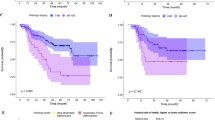

Univariate and multivariate analyses identified 40, 2003, and 45 quantitative features associated with distant metastasis, nodal metastasis, and histopathology (adenocarcinoma and squamous cell carcinoma), respectively. A machine learning model yielded the highest areas under the receiver operating characteristic curves of 0.92, 0.84, and 0.88 to predict the same previous patterns.

Several radiomic features (including wavelet energies, information measures of correlation and maximum probability from co-occurrence matrix, busyness from neighborhood intensity-difference matrix, directionalities from Tamura’s texture, and fractal dimension estimation) significantly associated with distant metastasis, nodal metastasis, and histology were discovered in this work, presenting great potential as imaging biomarkers for pathological diagnosis and target therapy decision.